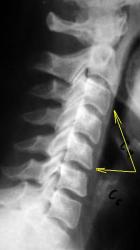

Разгибание.

Иллюстрация 3 – в положении максимального разгибания определяется смещение кзади тел С2, С3, С4 в виде ступенчатой комбинации, что свидетельствует о нестабильности в сегментах С2-С3, С3-С4, С4-С5.